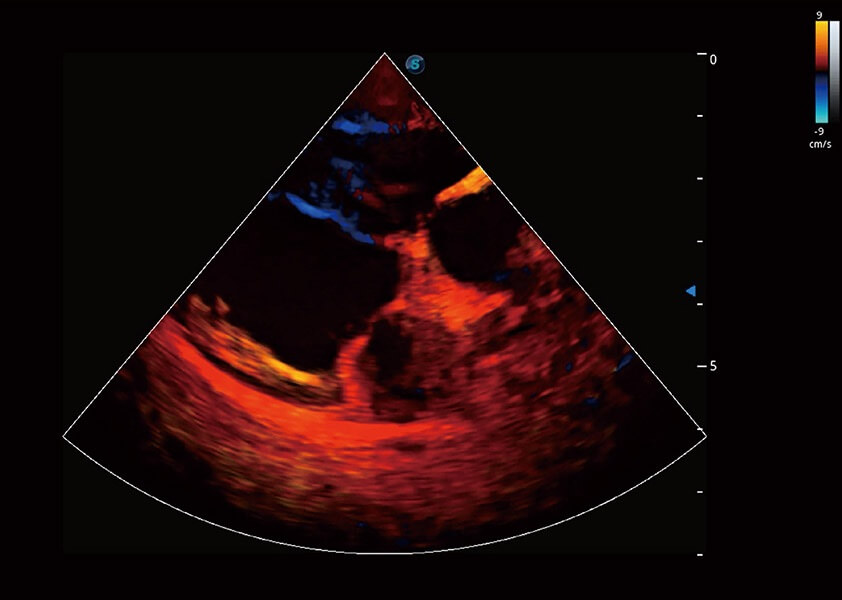

ProPet 60 作為一款高端臺式動物超聲設(shè)備,為動物醫(yī)生的日常診斷提供了一系列貼合動物臨床需求、解決臨床實際問題的高級成像功能。憑借全系列高清探頭,滿足醫(yī)生對腹部、心臟、生殖、淺表、肌骨等成像的所有需求,切實幫助您提升檢查效率,提高診斷信心。